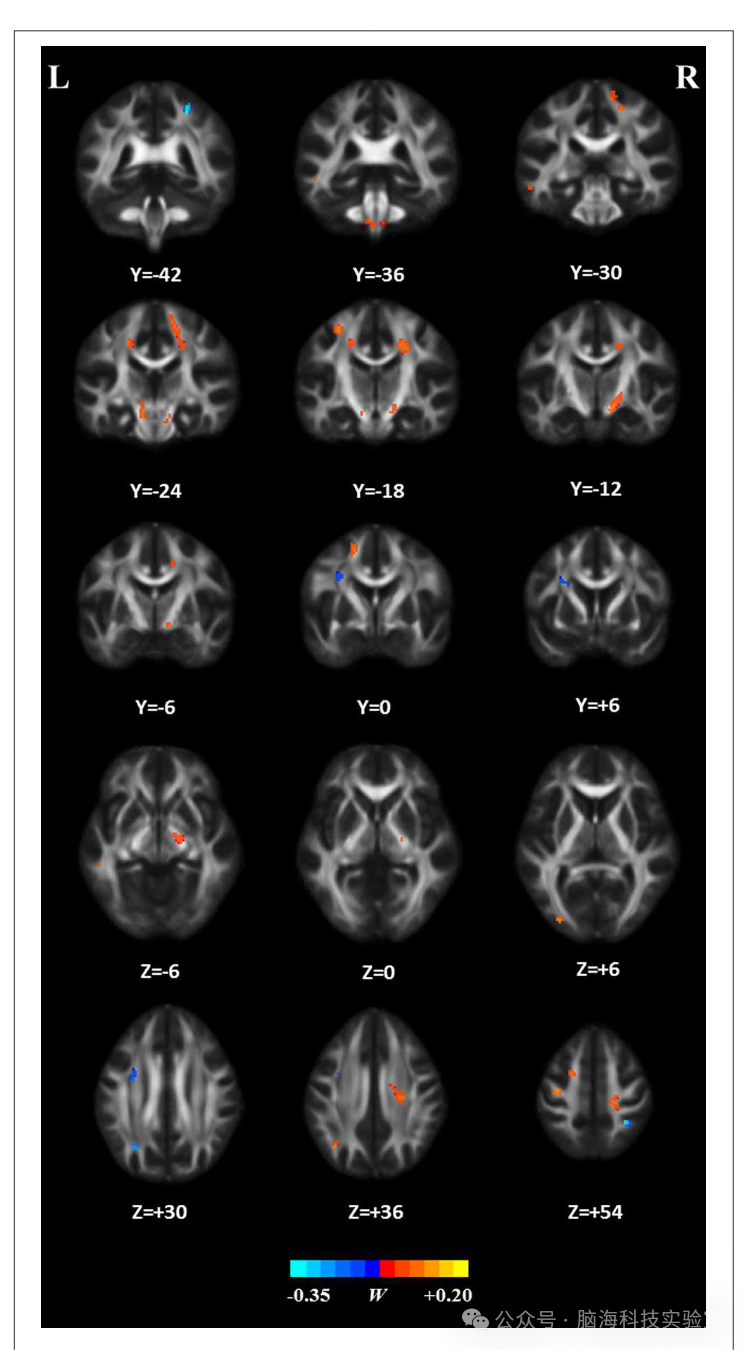

权重向量 w 用于指示两组之间最具区分能力的特征子集。因此,通过设定阈值为最大权重向量分数的≥10%,识别出对区分贡献最大的白质(WM)区域的FA值。表2 列出了这些区域的详细信息,并根据它们对组间区分的贡献(即权重向量 w)对这些区域进行了排序。图7 展示了 SVM 分析生成的属性权重的相关分布。在健康对照组(HC)中,FA值相对较高的白质区域位于多个部位,例如双侧放射冠和中央前回、右侧中央后回、右侧内囊后肢、左侧额上回、左侧角回、左侧颞中回、左侧枕中回、双侧中脑以及双侧桥脑和延髓;而在患者组中,FA值相对较高的白质区域位于左侧额叶、左侧缘上回和右侧缘上回。

图7

与以往的研究一致,研究发现ALS中FA降低的白质区域涉及双侧中央前回和皮质脊髓束(CST)通路,例如双侧放射冠、右侧内囊后部、双侧中脑、双侧桥脑和延髓。中央前回是初级运动皮层(PMC)的一部分。已有研究表明,ALS中PMC出现退行性变化,例如Betz细胞显著减少和皮层变薄。皮质脊髓束(CST)连接运动皮层和脊髓中的神经元,是与皮层对脊髓活动控制相关的纤维。CST的退行性变也是ALS的一个标志。总之,这些与运动相关的区域受损可能导致运动神经元功能障碍,并引发ALS患者所表现出的相关症状(例如,肌肉无力和自主控制能力丧失)。

FA降低的区域还包括一些非运动区域,例如右侧中央后回、涉及左侧额上回、左侧角回和左侧颞中回的左侧上纵束(SLF),以及涉及左侧颞中回和左侧枕中回的左侧下纵束(ILF),这与以往研究的结果一致。例如,已有研究表明,ALS中中央后回显著的皮层变薄,即初级体感皮层,与疾病的严重程度相关。此外,上纵束(SLF)连接额叶、顶叶和颞叶,并在语言功能中发挥关键作用,在ALS中受到破坏。同时,左侧下纵束(ILF)的损伤——该纤维主要与视觉处理、语言/语义功能以及情绪调节相关——已在ALS患者中被报道。因此,这些在非运动区域出现的损伤(表现为 FA 值降低)可能与 ALS 中报告的各种非运动功能障碍相关,例如感觉障碍、语言功能障碍,以及行为和精神异常。

相比之下,研究的结果显示ALS患者的多个大脑区域,包括左额叶、左顶下叶和右上顶叶的FA相对增加。推测这些变化可能与ALS的功能补偿或脑结构重组有关。与这一猜测一致,ALS中已经证明了几种补偿现象,如灰质体积增加或特定大脑区域过度激活所反映的那样。

在优化后的SVM模型中,FA值对分类贡献最大的白质区域主要涉及运动和非运动区域,包括双侧冠状辐射、中央前回、右侧后中央回、右侧内囊后肢、左侧额上回、左侧角回、左侧中颞回、左侧中枕回、双侧中脑、双侧脑桥和延髓。相比之下,ALS患者中FA值相对较高的区域包括左侧额叶、左侧角回和右侧顶上小叶。